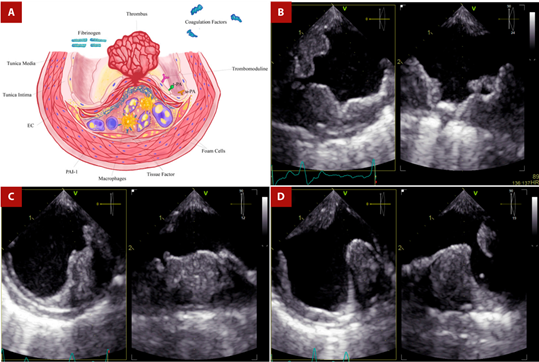

Figure 4 Shaggy aorta and thrombus. A. After rupture of the fibrous cap, coagulation molecules from the bloodstream come into contact with foam cells, tissue factor, and microparticles derived from apoptotic atheroma cells, triggering thrombus formation in the ruptured plaque. The thrombotic equilibrium will determine whether plaque rupture will culminate in the formation of a persistent, distant-migrating thrombus or in its dissolution. B. TEE - Proximal third of the descending aorta. Orthogonal images showing extensive mural thrombotic formation of irregular border that occupies up to one third of the arterial lumen, with small movable elements on its surface in the long axis. C. TEE - Middle third of the descending aorta. Orthogonal images show a crescent-shaped thrombus in the short-axis view. D. TEE - Distal third of the descending aorta. Orthogonal images of a wedge-shaped thrombus. Secondary thrombotic elements are in the opposite position to the initial one.